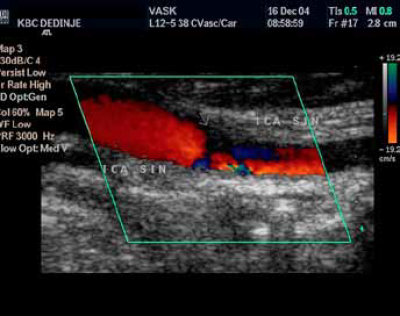

Duplex-ultrasonografski nalaz postoperativno: Turbulencija na mestu male neravnine na distalnom kraju endarterektomije,

In stent restenoza unutrašnje karotidne arterije nakon

PTA.